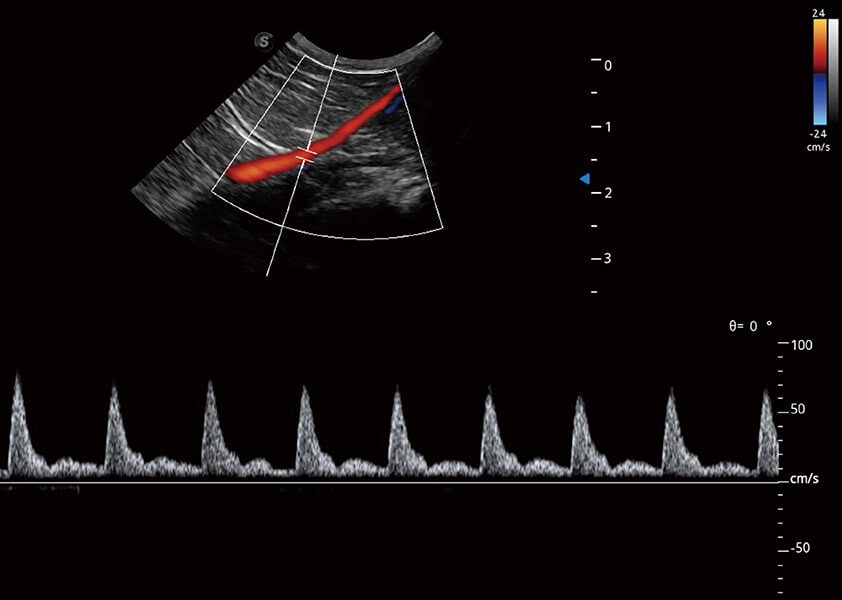

ProPet 60 作為一款高端臺式動物超聲設備,為動物醫(yī)生的日常診斷提供了一系列貼合動物臨床需求、解決臨床實際問題的高級成像功能。憑借全系列高清探頭,滿足醫(yī)生對腹部、心臟、生殖、淺表、肌骨等成像的所有需求,切實幫助您提升檢查效率,提高診斷信心。

動物是人類最親密的朋友和最值得信賴的伙伴。開立醫(yī)療也一直致力于探索動物專用的超聲影像解決方案。 全新推出的ProPet系列,是開立在動物超聲影像智能化、專業(yè)化、精準化的一次跨越式革新。動物不能用言語來表述自己的不適,通過超聲影像,ProPet系列搭建了動物醫(yī)生與不同物種溝通的“橋梁”,為動物醫(yī)生注入了“治愈之力”。